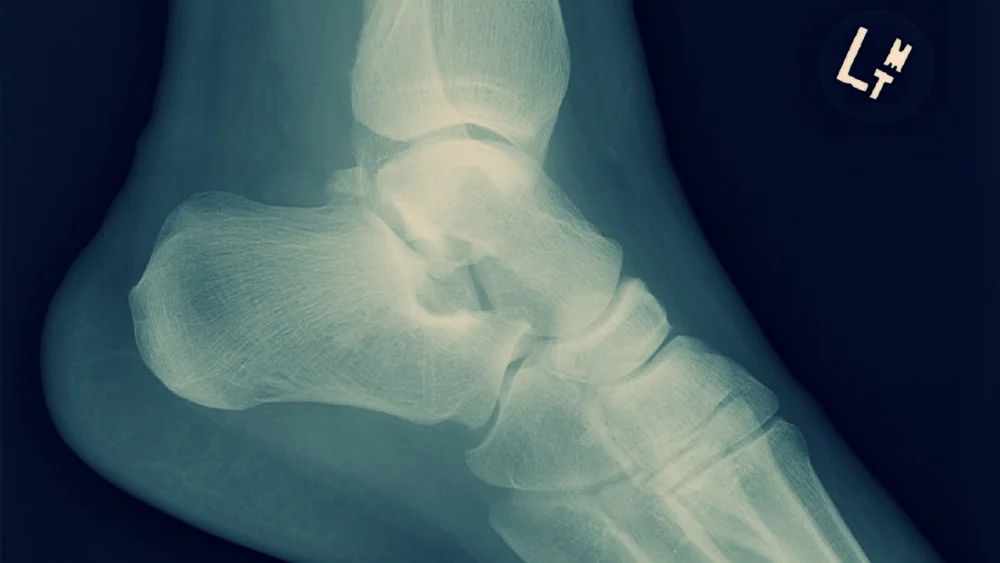

E – Bruising and wound to head, bruising, wound and deformity to left thigh